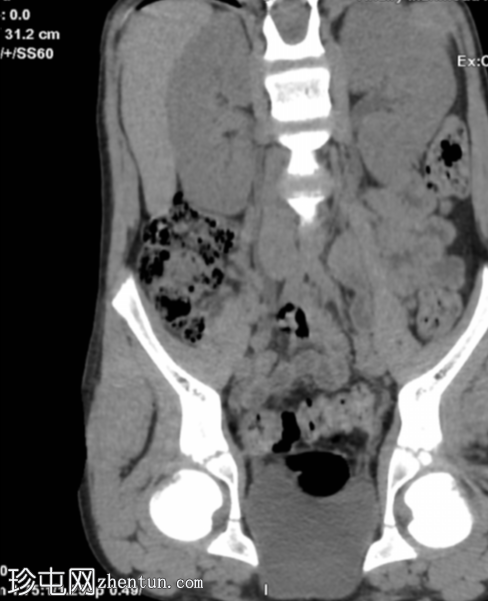

冠状位重建

显示输尿管显影

腹部和盆腔CT扫描结果正常。

泌尿系统正常。未见尿路结石或反流压改变。

本病例显示一名10岁男孩的腹部、盆腔和泌尿系统CT扫描结果正常。